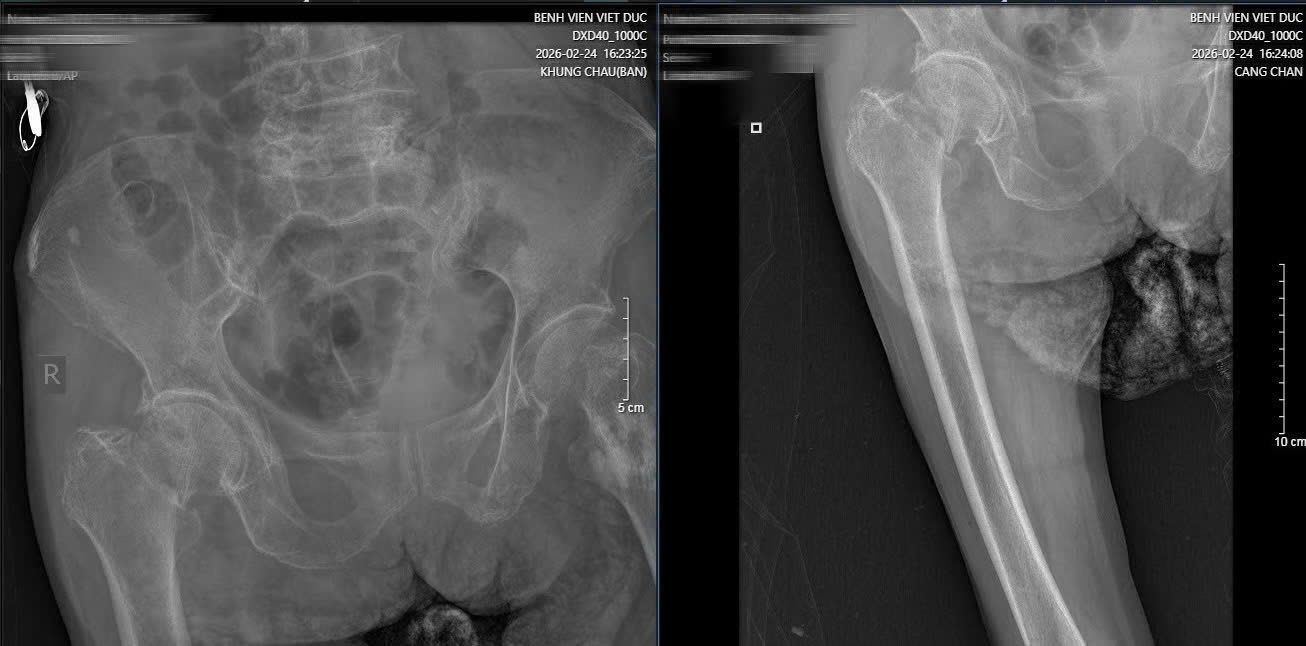

Hình ảnh phim X-quang cụ bà 89 tuổi nhập viện gãy cổ xương đùi phải và hình ảnh chụp CT ổ bụng và phát hiện khối u ruột non gây lồng ruột.

Trong quá trình kiểm tra tổng quát, các bác sĩ BV Hữu nghị Việt Đức phát hiện dấu hiệu bất thường ở vùng bụng. Kết quả chụp CT cho thấy cụ bị lồng ruột do u với khối lồng dài 165mm. Đây là tình trạng cấp cứu nguy hiểm, có thể gây tắc ruột và đe dọa tính mạng nếu không xử lý kịp thời.